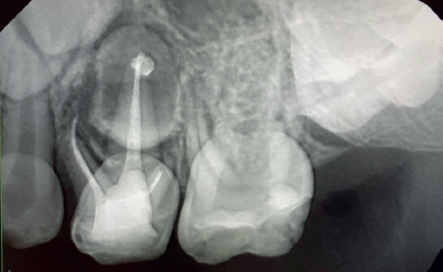

La fluorosis dental es una condición irreversible originada durante el desarrollo dental que genera pigmentaciones intrínsecas, alteraciones en el esmalte manifestadas a manera de manchas blancas, amarillas o marrones, que perjudican la estética y repercuten en el desenvolvimiento social. El presente reporte de caso clínico describe la combinación de los procedimientos de microabrasión y blanqueamiento dental, como alternativas en la eliminación de pigmentaciones dentales. Después del diagnóstico de la patología, verificación de ausencia de lesiones pulpares y caries, una explicación minuciosa a la paciente y obtención del consentimiento informado, se realizó limpieza de las superficies dentales y, bajo aislamiento absoluto, se procedió a realizar la técnica de microabrasión mediante ácido clorhídrico al 6,6% siguiendo las instrucciones del fabricante. Concluido el procedimiento y, observando que era posible mejorar aún más la estética, se decidió ejecutar el procedimiento de blanqueamiento dental, a base de peróxido de hidrógeno al 40% en el consultorio, seguido por peróxido de carbamida al 10% aplicado en el domicilio. Al finalizar el tratamiento se observó uniformidad en el color dental, conjugados con una evidente mejora en la calidad de vida y relación social de la paciente.